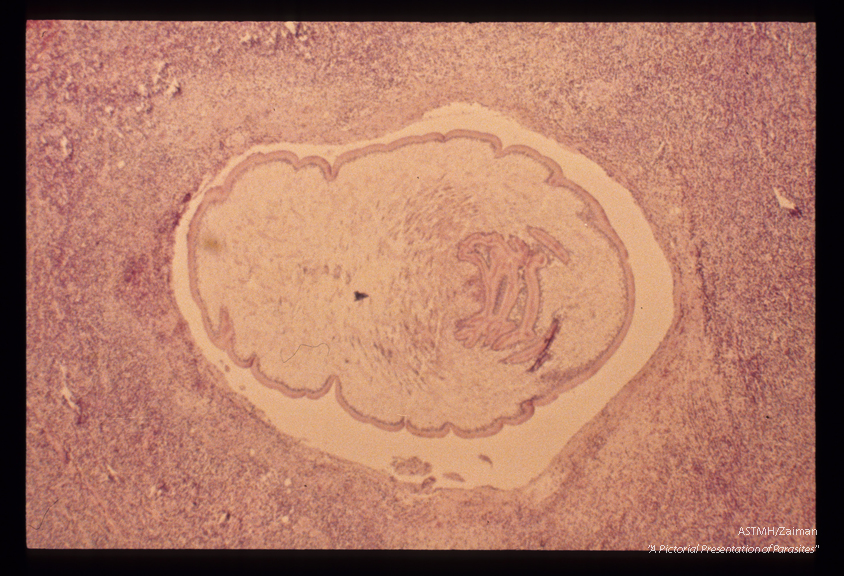

Human case. A cross section through the parasite shows typical tapeworm morphology. A dense neutrophilic infiltrate with many eosinophils is present in the adjacent muscle.

Sparganum